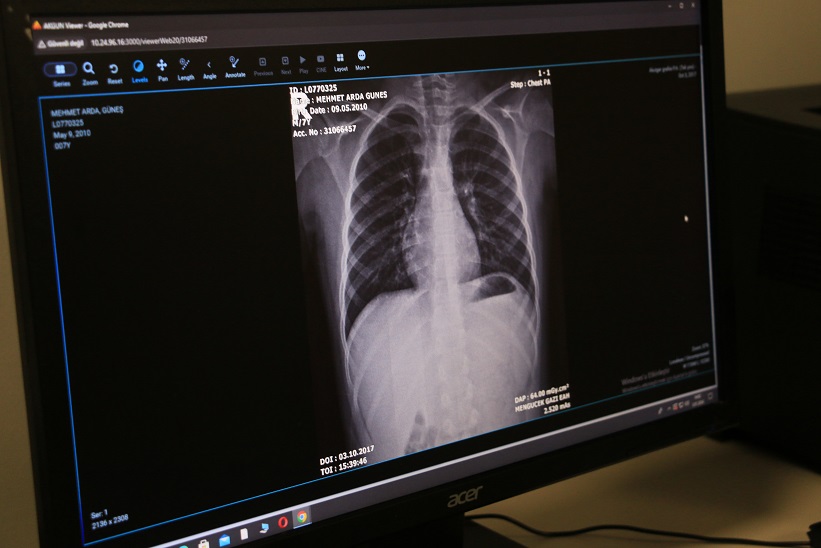

Akciğer kanseri tanı süreci; fizik muayene, akciğer grafisi, bilgisayarlı tomografi (BT), manyetik rezonans görüntüleme (MR), bronkoskopi ve biyopsi yöntemlerini kapsar. Ayrıca, genetik mutasyonların ve biyobelirteçlerin belirlenmesine yönelik moleküler testler, doğru tanı koyulması ve kişiye özel tedavi planlanmasında önemli rol oynamaktadır.